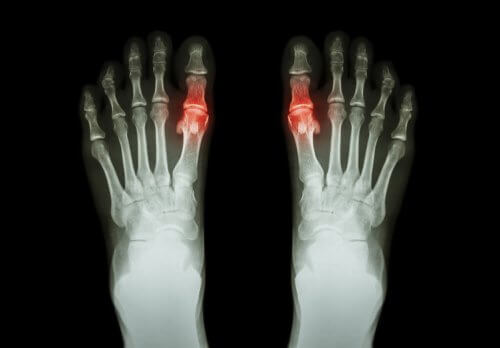

A doença geralmente se manifesta na forma de dor e dificuldade de mover a articulação afetada. Às vezes é acompanhada por rigidez na mesma área e inchaço. Ela pode acometer uma única articulação ou muitas ao mesmo tempo. Pode até ser simétrica ou não.

Cada tipo tem suas peculiaridades, e a duração dos sintomas é variável. Por exemplo, a artrite reumatoide é uma artrite simétrica que afeta pequenas articulações, como as dos dedos. A gota, por outro lado, geralmente aparece como artrite em uma única articulação.